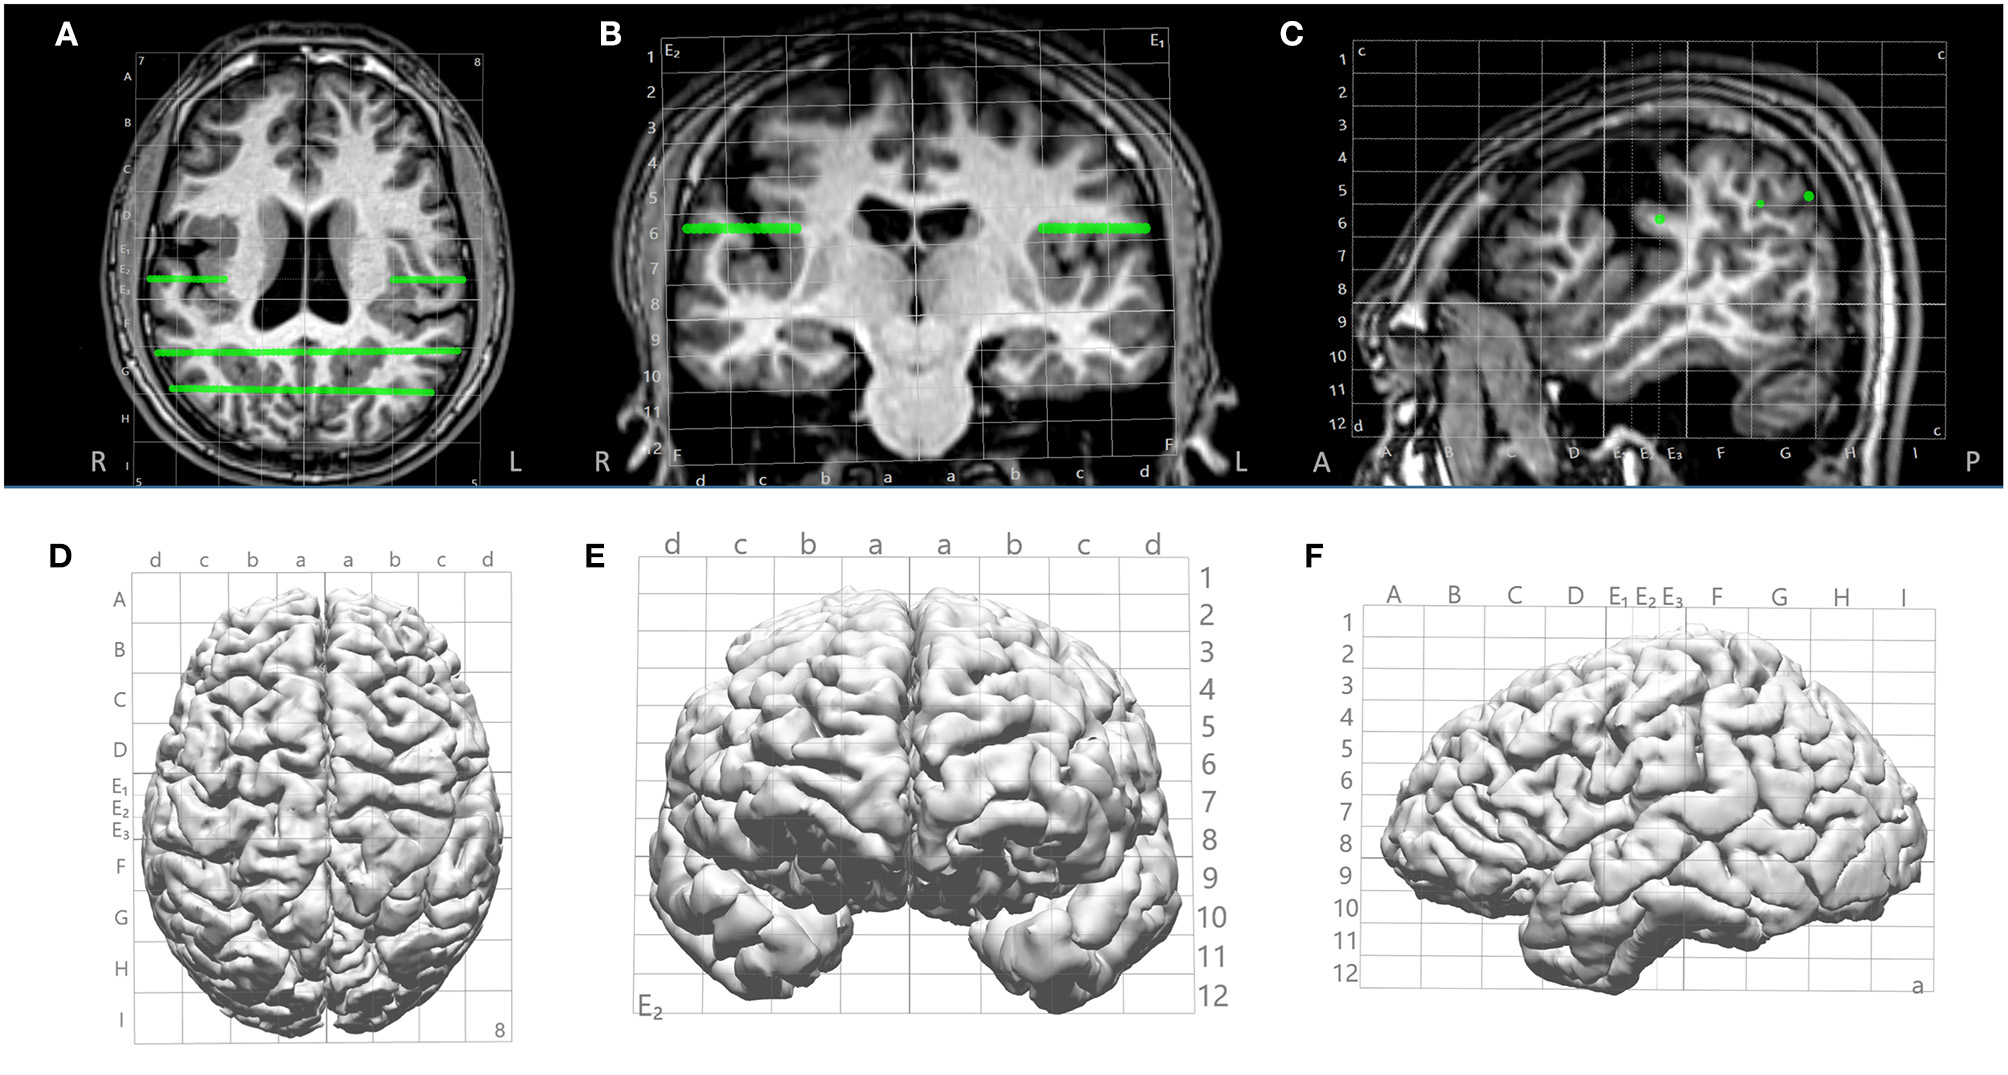

The Talairach grid was defined based on anterior commissure (AC) and posterior commissure (PC). The AC, PC and midsagittal (MS) points were first identified on the T1-weighed base image volume. Then, the boundary box of the brain was delineated on the sagittal view (anterior, posterior, superior and inferior boundaries) and axial view (lateral boundaries). The Talairach coordinates were defined with a proportional system consistent with its original definition (12). Specifically, on a sagittal view, sectors (columns) were defined as follows: the vertical AC (VCA) line and the anterior boundary of the brain was divided evenly into 4 parts: A, B, C, D. The vertical PC (VCP) line and the posterior boundary of the brain was divided evenly into 4 parts: F, G, H, I. On the sagittal view, levels (rows) were defined as follows: the distance between the AC-PC line and the superior boundary of the brain was divided evenly into 8 parts. The distance between the AC-PC line and the inferior boundary of the brain was divided evenly into 4 parts. On the coronal view, the columns were defined by dividing into 4 parts from the mid-sagittal to the most lateral boundary of the brain, for each hemisphere. Columns are named a, b, c and d from mesial to lateral. The sectors and levels were automatically shown after the initialization steps are done to identify AC, PC, MS, VCA, VCP and brain boundary box. This is illustrated in Figure 2.

Figure 2

Illustration of Talairach grid defined based on AC, PC and MS points identified on the 3D T1-weighted base image. (A–C) 2D overlay of the Talairach grid on coronal, axial and sagittal MRI; (D–F) 3D overlay of the Talairach grid on cortical surface (axial, coronal and saggital). Green lines indicate electrode trajectories.